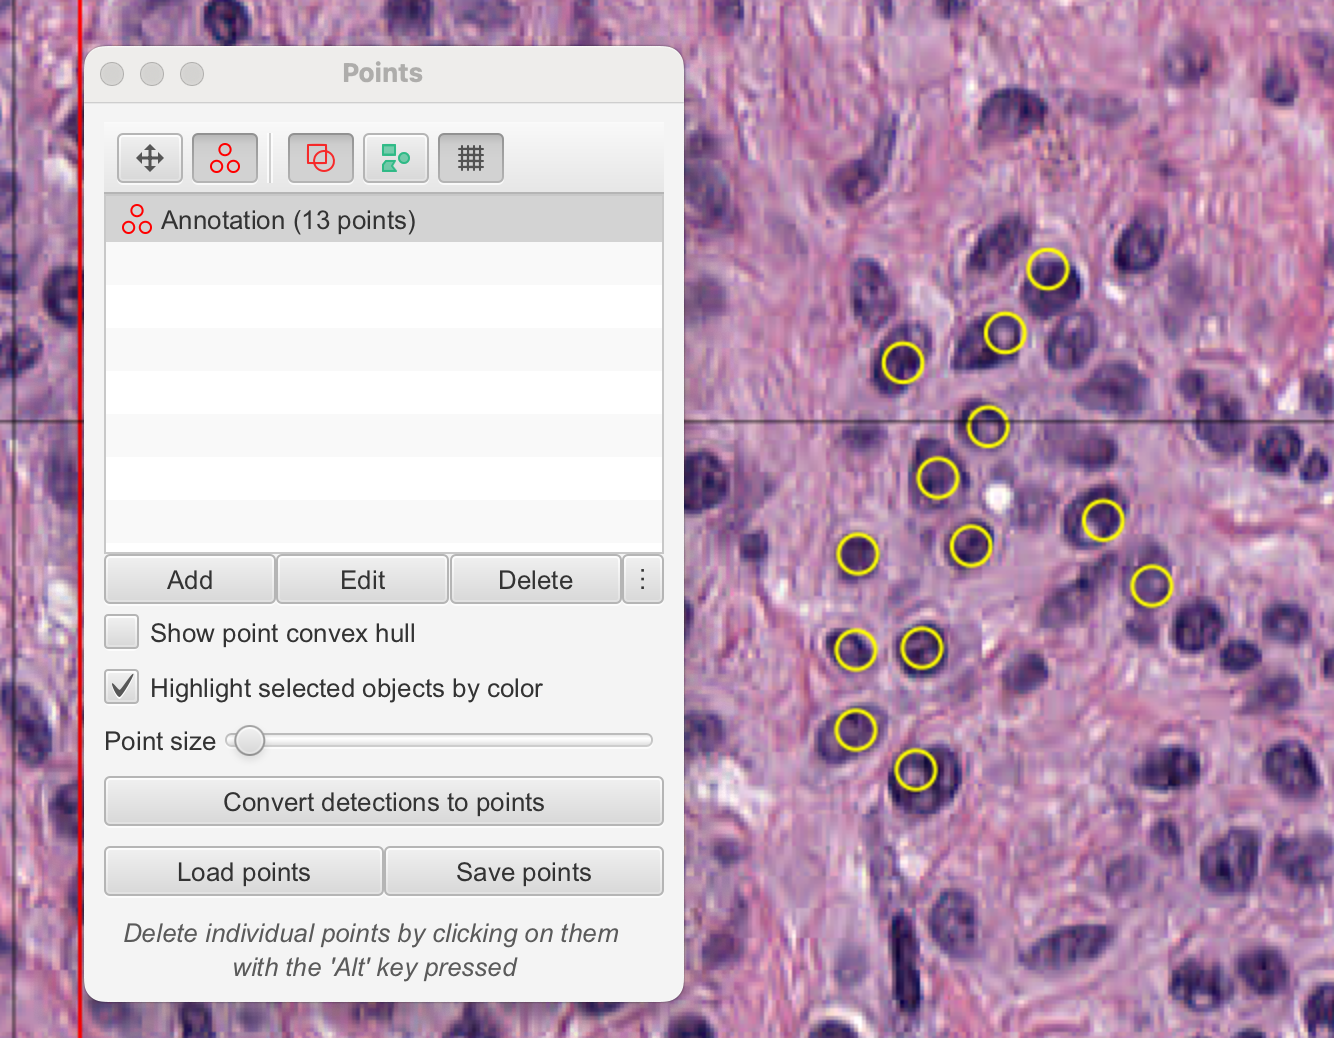

四、手动计数

计数是病理学和生物图像分析中的常见任务。

本节描述了如何使用QuPath手动计数不同类型的细胞——在这里,阳性(棕色)和阴性(蓝色)肿瘤细胞经过Ki67染色。

本节中描述的工具可以用于所有类型的手动计数任务。然而,我们将回到“细胞检测”和“细胞分类”部分,展示如何在QuPath中使用更复杂的工具来自动化细胞计数任务的某些或全部。

4-1:选择区域

首先的任务是在切片中找到一个合适的区域,在该区域中应计数细胞,使用在“查看图像”部分中描述的控制器在切片中浏览。

完成此操作后,可以选择(但很有帮助)在图像上叠加一个网格,以协助在固定区域进行计数。这可以通过简单地点击显示网格的工具栏按钮来完成。

4-2:点击细胞

为了开始认真计数,请在工具栏中选择点工具Point tool。这将自动打开一个计数面板,其中包含一个单独的点注释列表。然后,您可以在图像上开始点击,每次点击都会创建一个点。

注意

在此阶段,您应该只点击同一类细胞(例如阳性细胞)。

在您点击了一段时间后,您可能希望开始计数另一类细胞(例如“阴性”)。在计数面板中按添加按钮将开始一个新的注释来收集您的新点集,但您可能希望更清楚地区分点。

您可以通过双击计数面板中的条目,并设置更详细的名字和颜色来实现这一点。无论何时在图像上点击,您都会向列表中选定的条目添加点。